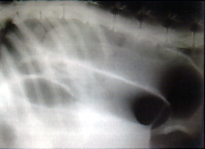

La imagenología constituye un certero aliado en este tipo de pacientes. Radiográficamente, es común encontrar incremento de la radioluscencia en la cavidad abdominal, visualizándose las asas de intestino dilatadas y repletas de gas en su interior, generando el diagnóstico típico de Íleo gaseoso de distribución localizado y, en la mayoría de las ocasiones, de severa intensidad. Ver foto 4.

torsion4

Foto 4: íleo Gaseoso Localizado Severo.